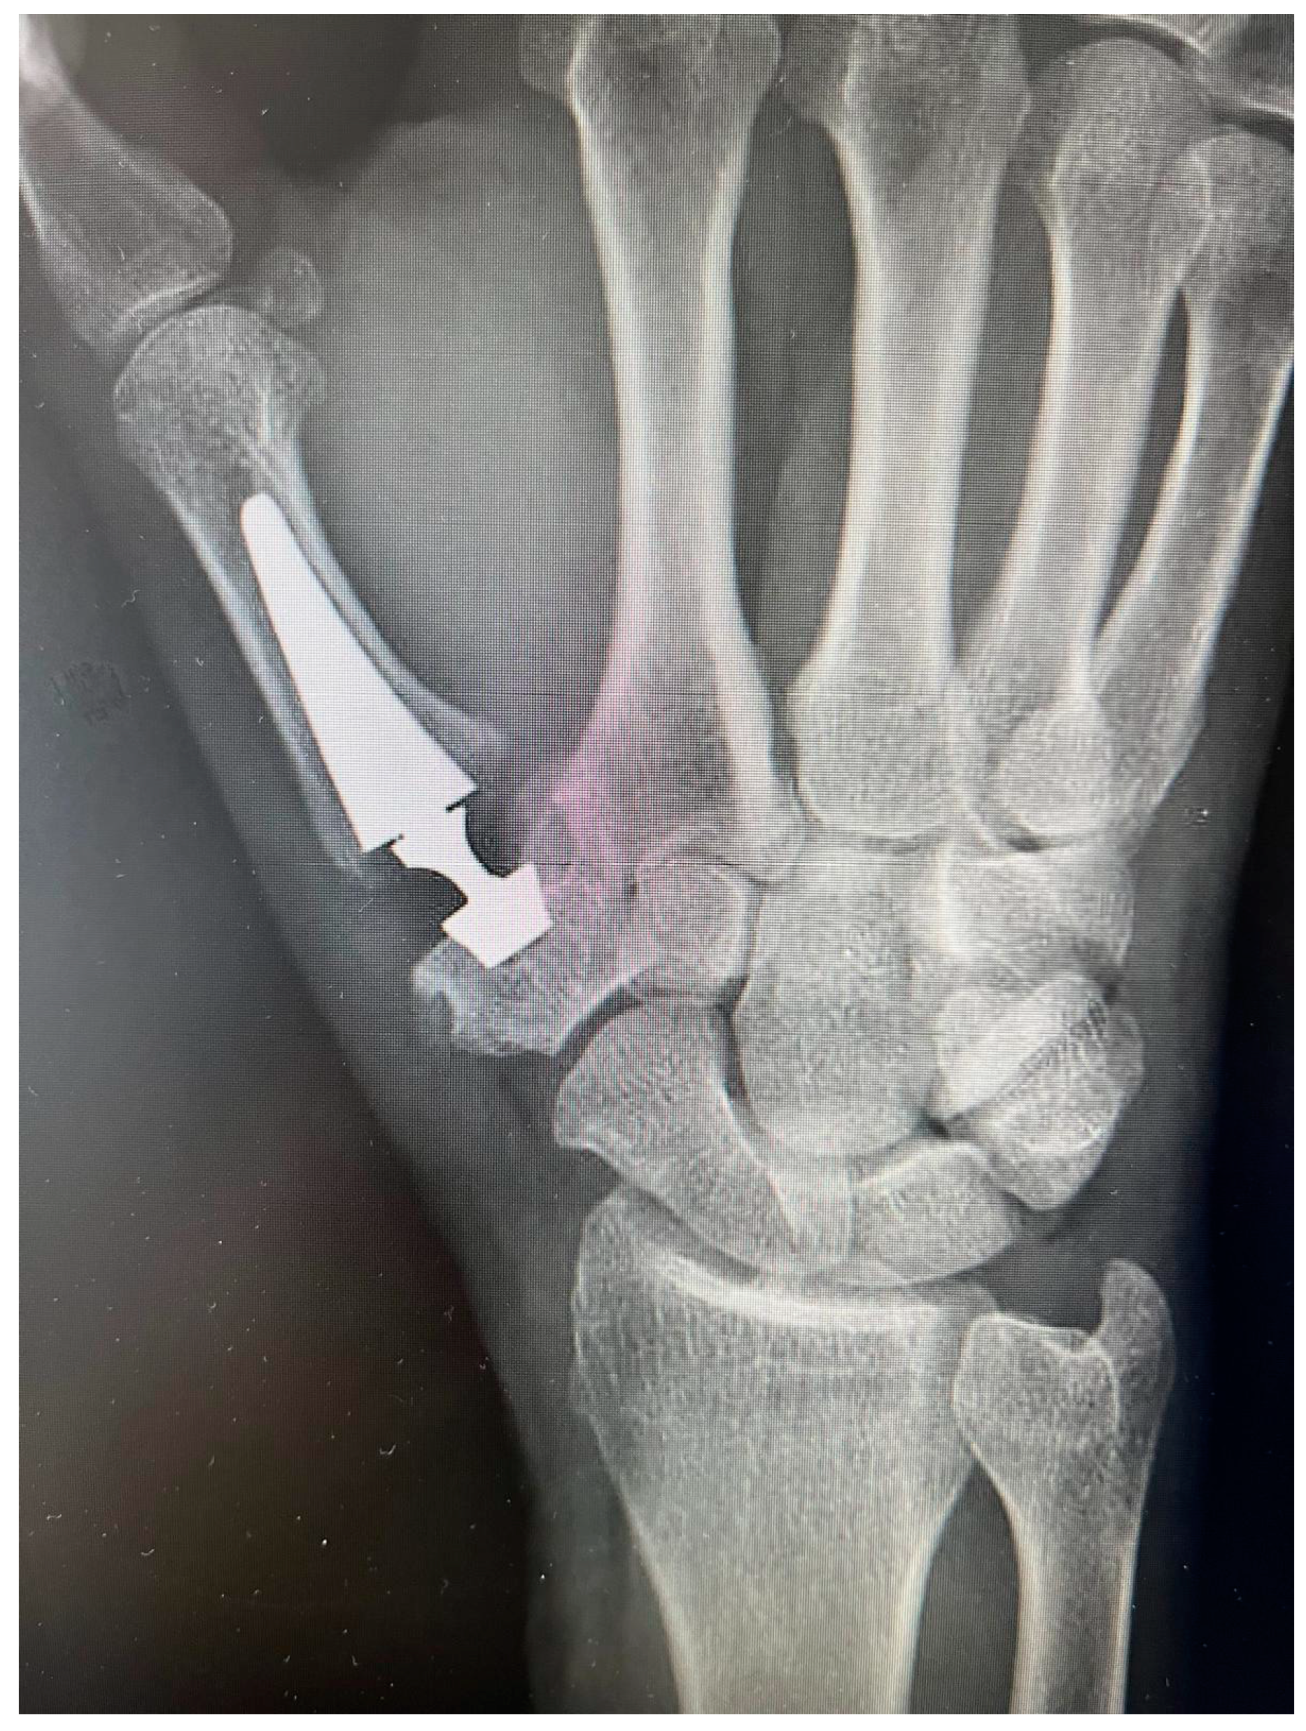

2.2. Prosthesis Design

2.3. Surgical Technique